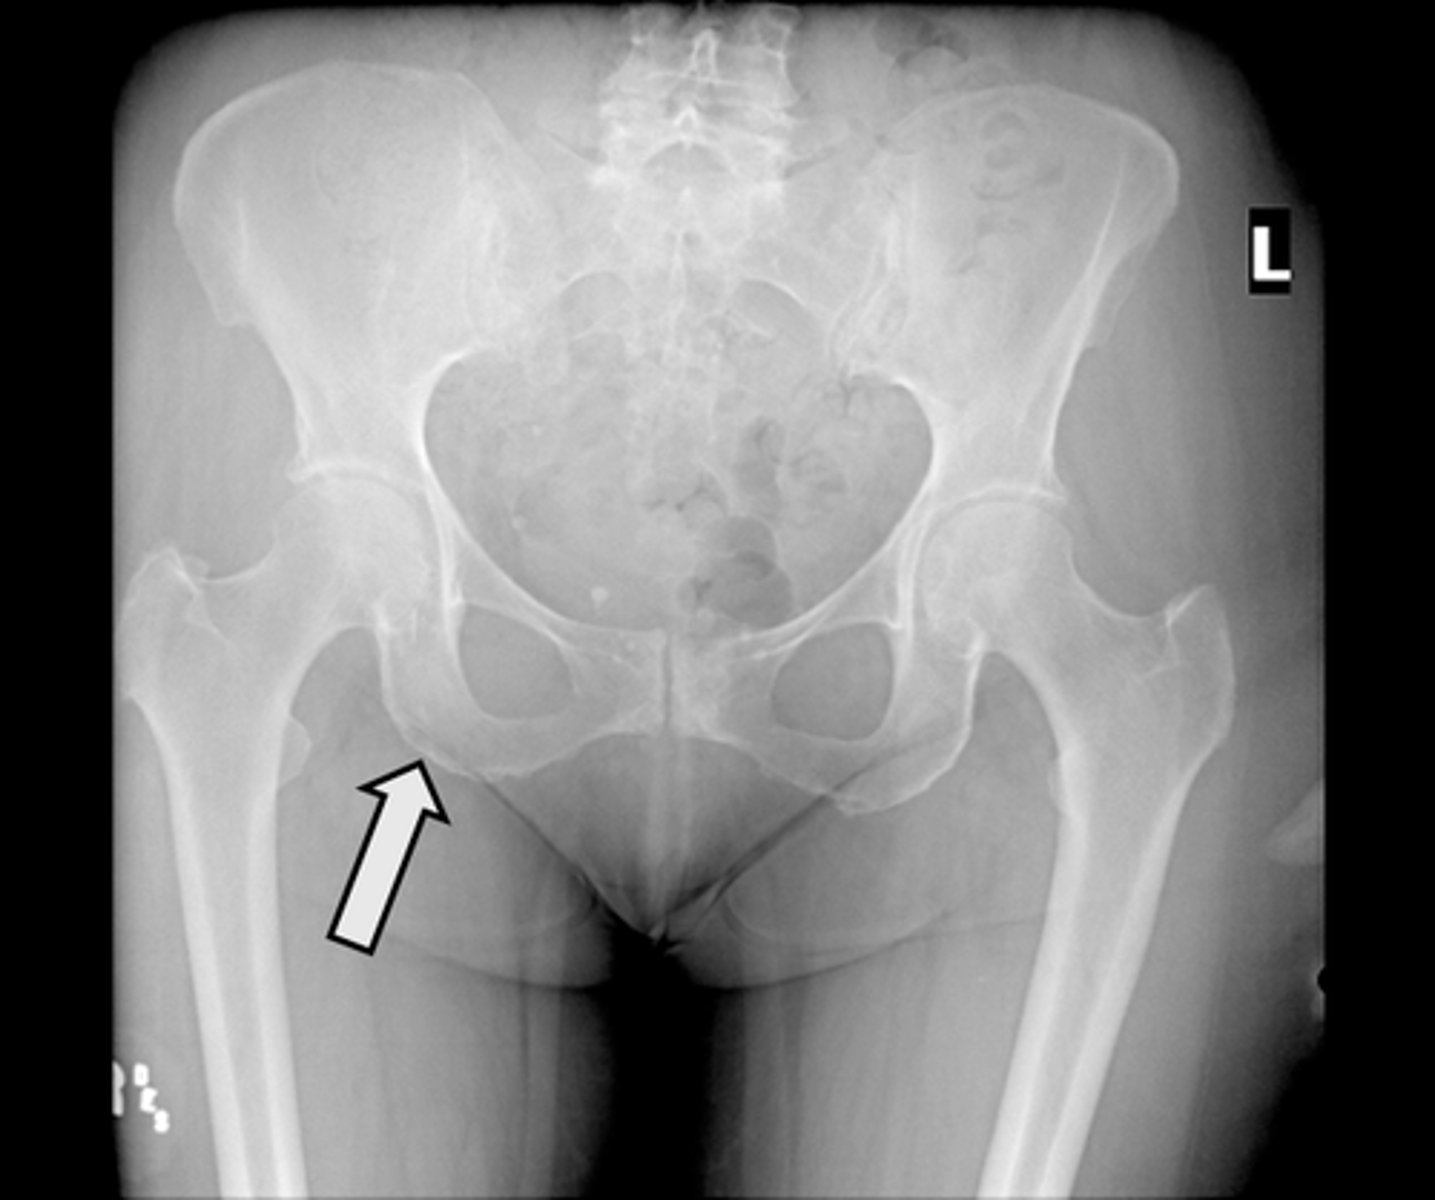

AP pelvis

What is the image?

Nonfused greater trochanter

What is indicated in the image?

<p>What is indicated in the image?</p>